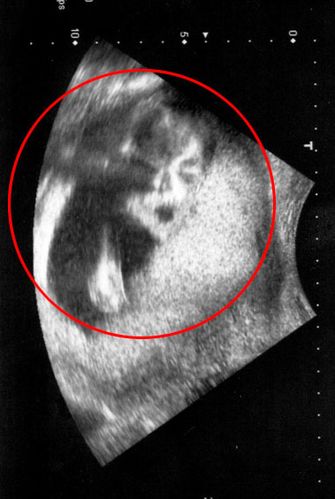

• 第一次B超:孕6-8周

孕妇孕期到底需要做多少次B超才合适?不同阶段有哪些必须检查的项目?-第1张图片-郑州医学网

(图片来源网络,侵删)

• 目的:

1. 确认是否为宫内妊娠: 排除宫外孕的风险。

2. 确认孕周: 通过测量胎芽大小(头臀长),可以精确推算预产期,尤其对于月经不规律的女性来说至关重要。

3. 判断胚胎数量: 确定是单胎还是多胎。

4. 查看胎心搏动: 确认胚胎是否存活,通常在孕7周左右可以看到胎心。

• 特殊情况: 如果有阴道出血、腹痛等异常情况,医生可能会建议做阴道B超,它能更清晰地观察早期情况。